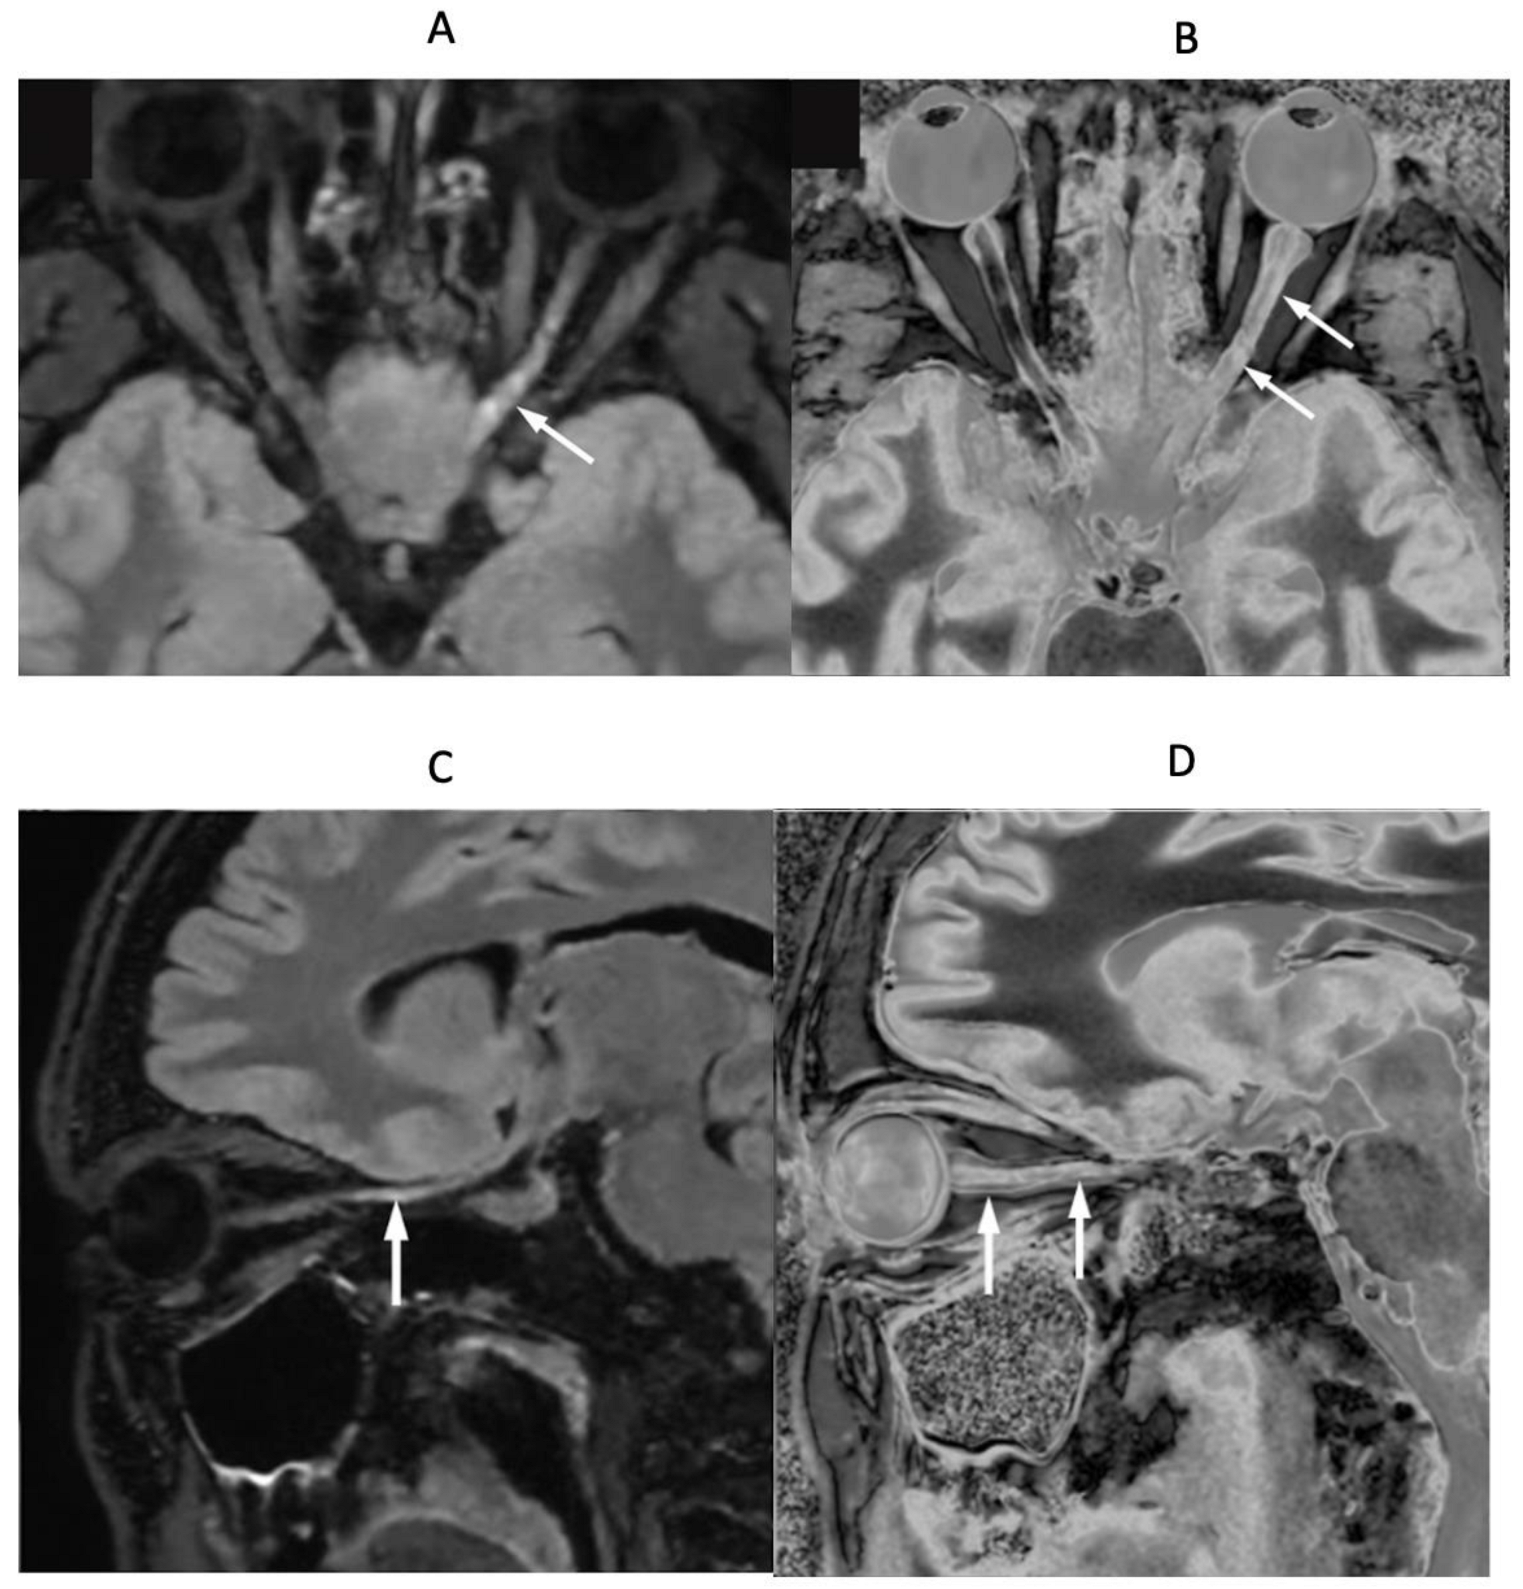

In a patient with optic neuritis and suspected MS, Figure 17A,B (upper row) show axial fat saturated T2-FLAIR (Figure 17A) and narrow mD dSIR (Figure 17B) images of their optic nerves. Figure 17C,D (lower row) show parasagittal oblique fat saturated T2-FLAIR (Figure 17C) and narrow mD dSIR (Figure 17D) images of the left optic nerve. The right optic nerve appears normal in Figure 17A,B. The left optic nerve shows a distal abnormality on the T2-FLAIR axial and parasagittal images (white arrows), but shows proximal and distal abnormalities on the corresponding dSIR images (white arrows).

Figure 17.

Patient with optic neuritis and suspected MS. The upper row shows axial fat saturated T2-FLAIR (A) and narrow mD dSIR (B) images. The lower row shows matched oblique fat saturated T2-FLAIR (C) and narrow mD dSIR (D) images through the left optic nerve. Distal changes are seen in the left optic nerve on the T2-FLAIR images (arrows) but both proximal and distal changes are seen in the left optic nerve on the dSIR images (arrows).